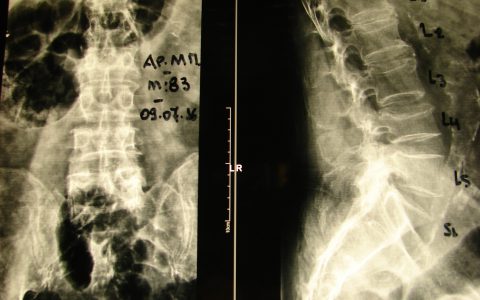

Η κα Πα.Γι. 61 ετών, έπασχε από σκολίωση της σπονδυλικής στήλης από νεαρή ηλικία. Σε ηλικία περίπου 40 ετών άρχισε να παραπονιέται για πόνο στην οσφυϊκή μοίρα της σπονδυλικής στήλης. Η αντιμετώπιση του πόνου ήταν συντηρητική. Προοδευτικά ο πόνος επιδεινώθηκε παρά την αγωγή, γι’ αυτό αναζήτησε περαιτέρω θεραπευτική αντιμετώπιση. Εικ 1: Προεχειρητικές ακτινογραφίες της σπονδυλικής